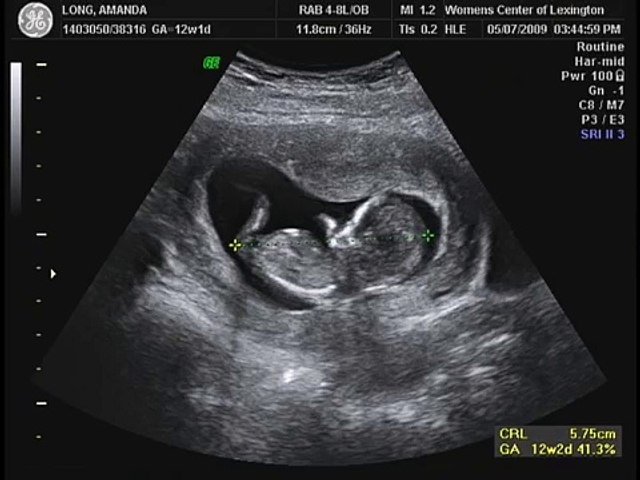

This is a special family event However, room space limitations allow only three additional individuals Is 29 Weeks Pregnancy Update 2 Ultrasounds (Including a 3D!) by Jen on I have so much to catch you up on in my 29 weeks pregnancy update I had a pretty big appointment last week at 28 weeks that included an ultrasound and then today I had an elective 3D ultrasound that was just the coolest thing ever Let's get to it!16 to Weeks Best time to peek at the baby's entire body and to determine genderBaby's face is still growing, so facial features are still developing 2D and a glimpse at 3D are best at this time to 26 Weeks Best time to see your baby's face for the first timeThe face is more defined, and you can peek at the hands and feet 2D, 3D, and HD Live scans are best at this time

This page shows typical 3D ultrasound images from 11 to 36 weeks All of these images were taken here at SonoSmile which does amazing 3D ultrasound in Ocala Florida 2D, 3D, and 4D Ultrasound Ocala Florida SonoSmile 4D Fetal Imaging 24 Weeks 25 Weeks 26 Weeks 27 Weeks 28 Weeks 29 Weeks 30 Weeks 31 Weeks 32 Weeks 33 Weeks 34 WeeksPregnancy week 24 ultrasound scan Jenna Keller sent in this 3D ultrasound scan of her baby boy, taken at 24 weeks Looking like he's having a snooze!Jeff & Elena's little Baby (Alexandra) 3d ultrasound Dec 16,11This was so cool!

3D ultrasound picture of baby at 24 weeks pregnant Details on 24th week pregnancy symptoms & baby development >> > Select Week of Pregnancy 1 Week Pregnant 2 Weeks Pregnant 3 Weeks Pregnant 4 Weeks Pregnant 5 Weeks Pregnant 6 Weeks Pregnant 7 Weeks PregnantAt 24 weeks, a baby is about 8 1/4 inches (213 centimeters) from the top of the head to the bottom of the buttocks (known as the crownrump length ) A baby's height is approximately 12 inches or 1 foot (304 centimeters) from the top of the head to the heel (crownheel length) 1 This week, a baby typically weighs 24 ounces or 1 1/2 At 24 weeks pregnant, your baby's facial features are becoming more defined At this rate, your little one will be ready for all those photos you'll snap after you give birth!

24 Weeks Baby and Fetus Development The discomforts caused by pregnancy in 24th week can be reduced if one exercises or attend the prenatal classes The weight of the baby in the 24th week pregnancy ranges from 1 to 15 pounds The lungs of the baby in this time has branches and special cells that helps in producing surfactant are produced Today the we will be talking about your Normal 24week pregnancy and ultrasound, as usual you are going to find ultrasound images plus all you need to know about your 24 week pregnancy on this post, 3D Fetal face Uterine fibroid Ovarian cysts Nose and lips Share the blog to your social media Follow me 3D ultrasound pic at 24 weeks I just went to a place where you go to find out the babies gender and see 3D ultrasound pictures My picture makes me more scared then anything because the one eye that i see looks like its not there and its black and to put it simply, it looks like someone cut the babies eye out and sewed it back together and the nose looks so far up her